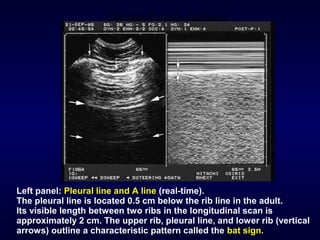

Left panel: Pleural line and A line (real-time).

The pleural line is located 0.5 cm below the rib line in the adult.

Its visible length between two ribs in the longitudinal scan is

approximately 2 cm. The upper rib, pleural line, and lower rib (vertical

arrows) outline a characteristic pattern called the bat sign.

Normal lung surface Leftpanel: Pleural line and A line (real-time). The pleural line is located 0.5 cm below the rib line in the adult. Its visible length between two ribs in the longitudinal scan is approximately 2 cm. The upper rib, pleural line, and lower rib (vertical arrows) outline a characteristic pattern called the bat sign.